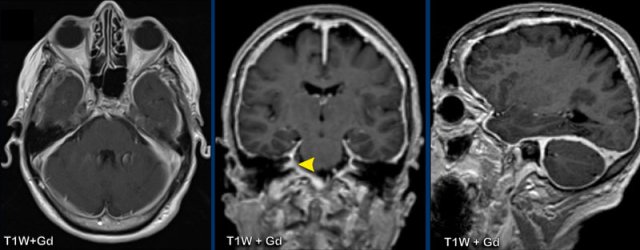

These images are of a 55-year old immunocompromised patient, who presented with cognitive complaints and headache.

Images

FLAIR shows non-supressed enhancing CSF in the subarachnoid

space.

Look along the cerebellar foliae, these are hyperintense on FLAIR (black arrowheads).

There is faint leptomeningeal enhancement (yellow arrowhead).

Furthermore there is high FLAIR signal at the

perivascular spaces in the semioval centre with enhancement.

Conclusion

This turned

out to be cryptococcal meningitis.

The spread

along the perivascular spaces in an immunocompromised patient is suggestive.

Sometimes in these patients there are also pseudocysts.

In this patient there was also enhancement of the trigeminal nucleus (black arrowhead), the dura and both optic nerves.

The enhancement around the left optic nerve is best seen on the axial image (yellow arrowhead), while the enhancement on the right is best seen on the coronal image (white circle).